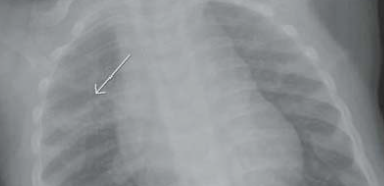

- Métaphyses floues (bandes claires), élargies en cupules

- Atteint aussi les jonctions Chondro-costales (bosse palpable)